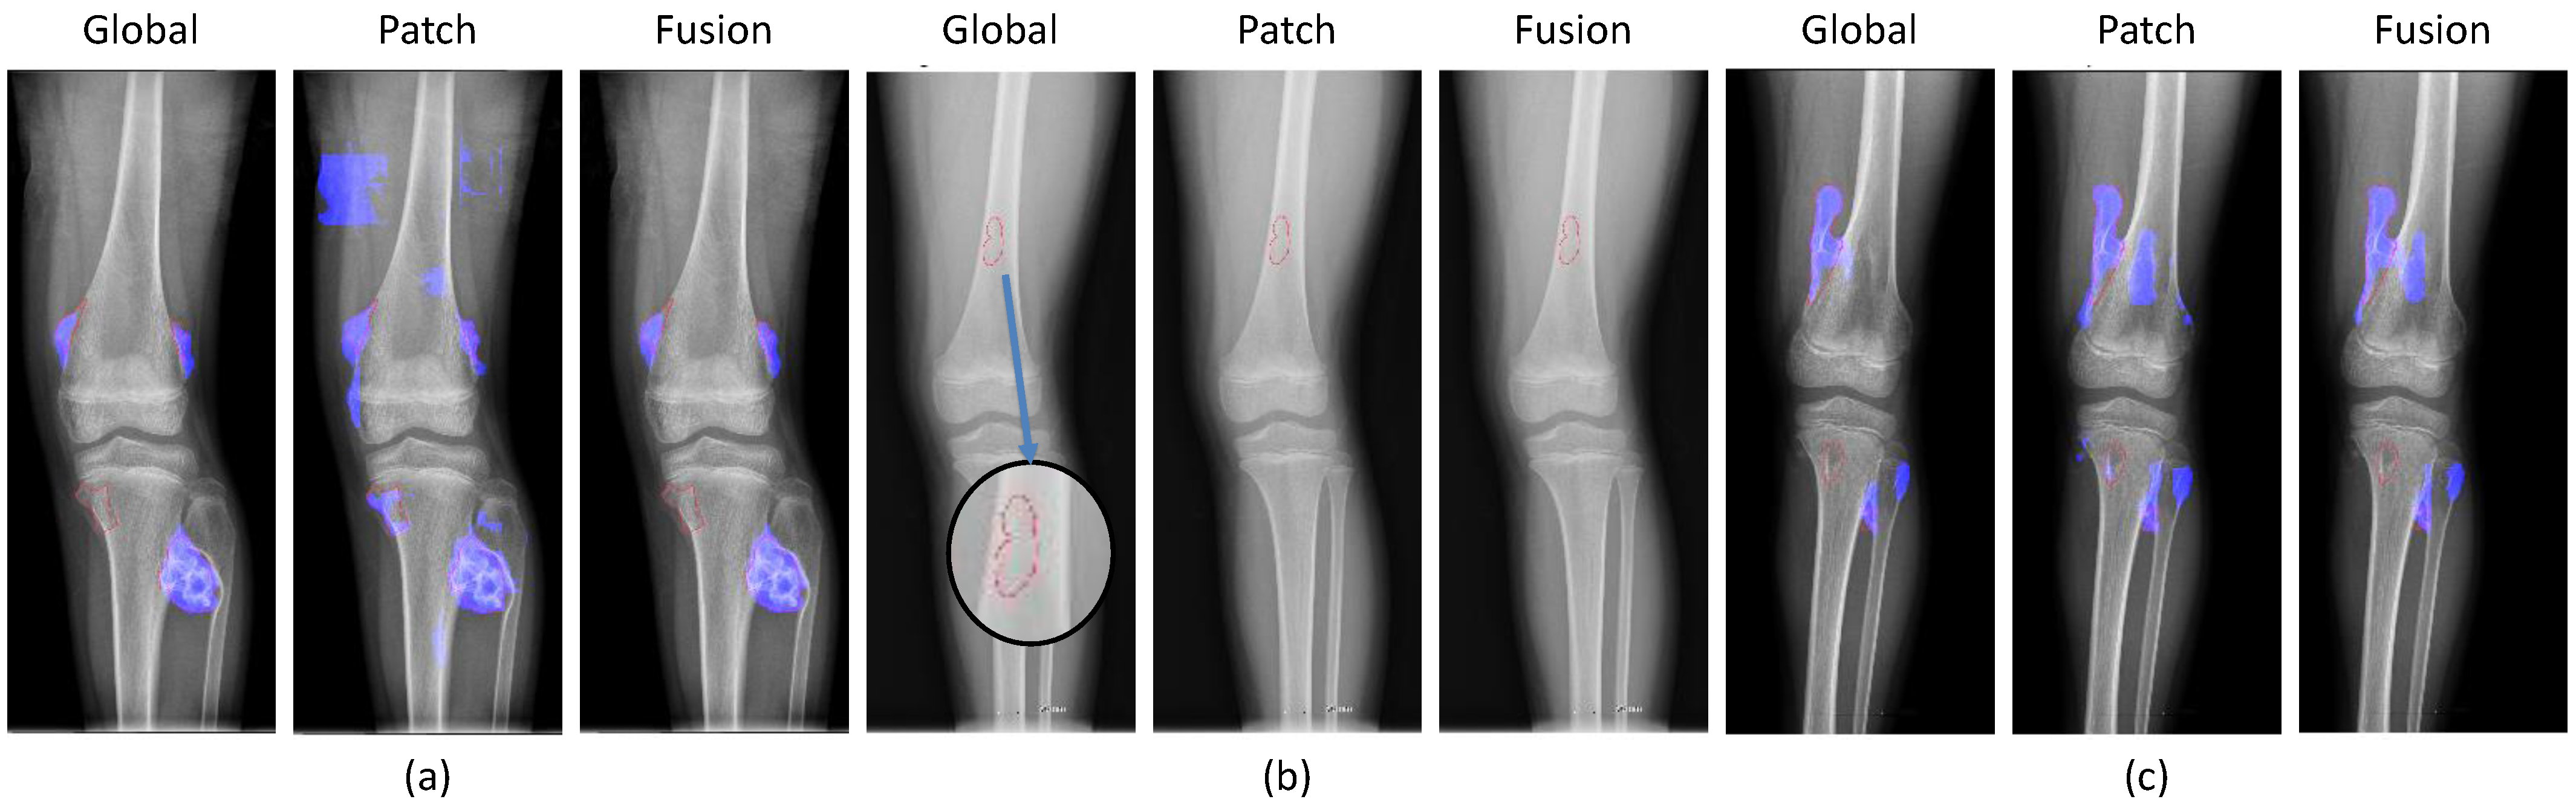

2.2.2. Global and Patch-Based Models

3.1. Experiments on Tumor Segmentation

Appendix B.3. Fusion of Global and Patch-Based Models